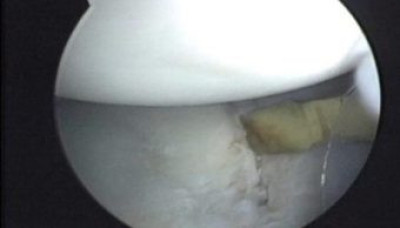

Durante el exámen se comprueba la luxación anterior del hombro